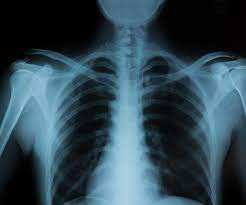

It is the common imaging test that is used by doctors for years to check what is happening inside the people’s body that too without any incision. It helps them to diagnose, monitor, and then treat the issues going on. There are different kinds of X-rays that are used for different purposes.

Medical applications of Digital X-Ray:

- Medical imaging

- Detection of the pathology of the skeletal system

- Identify bone structures

- Detection of intestinal obstruction

- Diagnostic imaging

- Detection of some disease processes in soft tissue